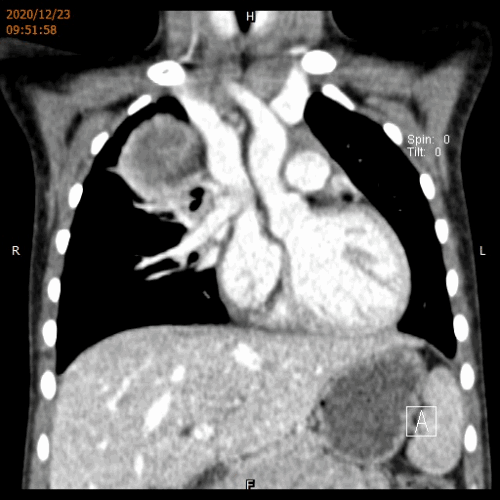

经过多方打听,辗转求医,小艺艺一家来到了省立医院儿外科胸外专业组。根据患儿影像学检查等相关病历资料,吴荣德教授组织科内医师对患儿病情进行讨论分析,认为肿瘤来源于后纵隔,巨大肿瘤压迫右肺导致肺不张,进而合并肺部感染才导致了小艺艺反复发热、咳嗽,建议患儿尽快行手术治疗。

术前CT动图

经过缜密的术前准备,12月30日,在吴荣德教授带领下,刘伟主任医师、郭锋副主任医师为小艺艺进行了胸腔镜微创手术治疗,术中发现患儿的肿瘤大小约8x7x6.5cm,占据了右侧胸腔的上半部分,与周围血管、神经、气道关系较密切。经过仔细游离与解剖,完整切除了整个肿瘤,并顺利将肿瘤从仅2.5cm长的手术切口中分块取出。术后顺利拔除胸管,右肺复张良好,症状明显减轻,顺利出院。解除了病痛的小艺艺,恢复了往日的活泼,脸上充满了灿烂的笑容。